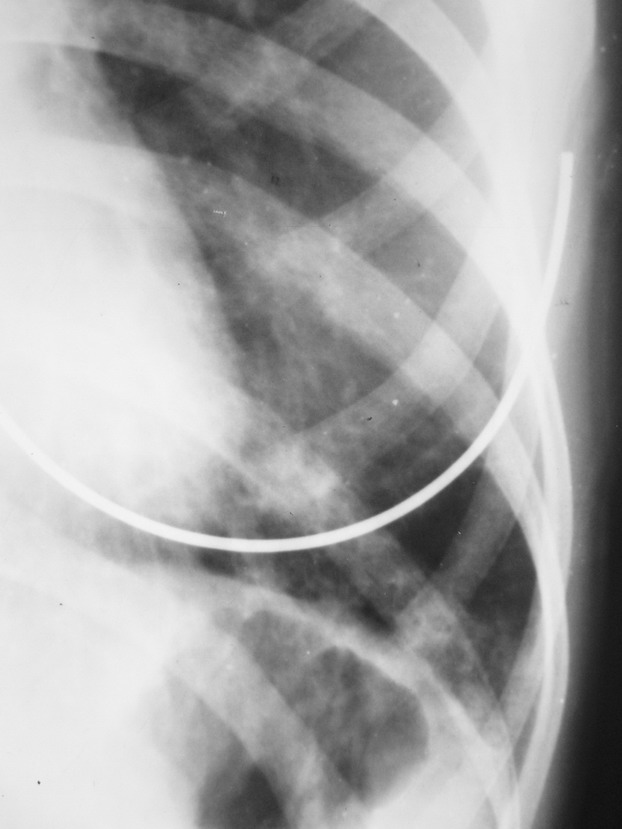

患者 女 22岁 咳嗽 咳痰 体温37.4度 白细胞在正常范围 于十日前诊断左肺下炎症 在个体诊所抗炎治疗9日 用药不详(未做过敏实验)今日复查 该患半年前曾在外院诊断过左肺下炎症 后治愈 该患者体质瘦弱

今日复查片: